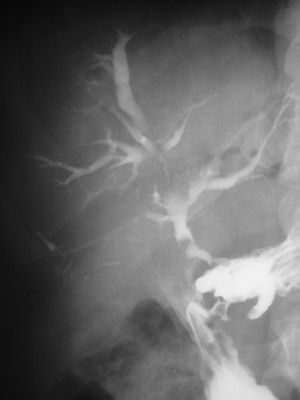

| Abdominal CT with right colocutaneous fistula and associated subcutaneous emphysema. | |